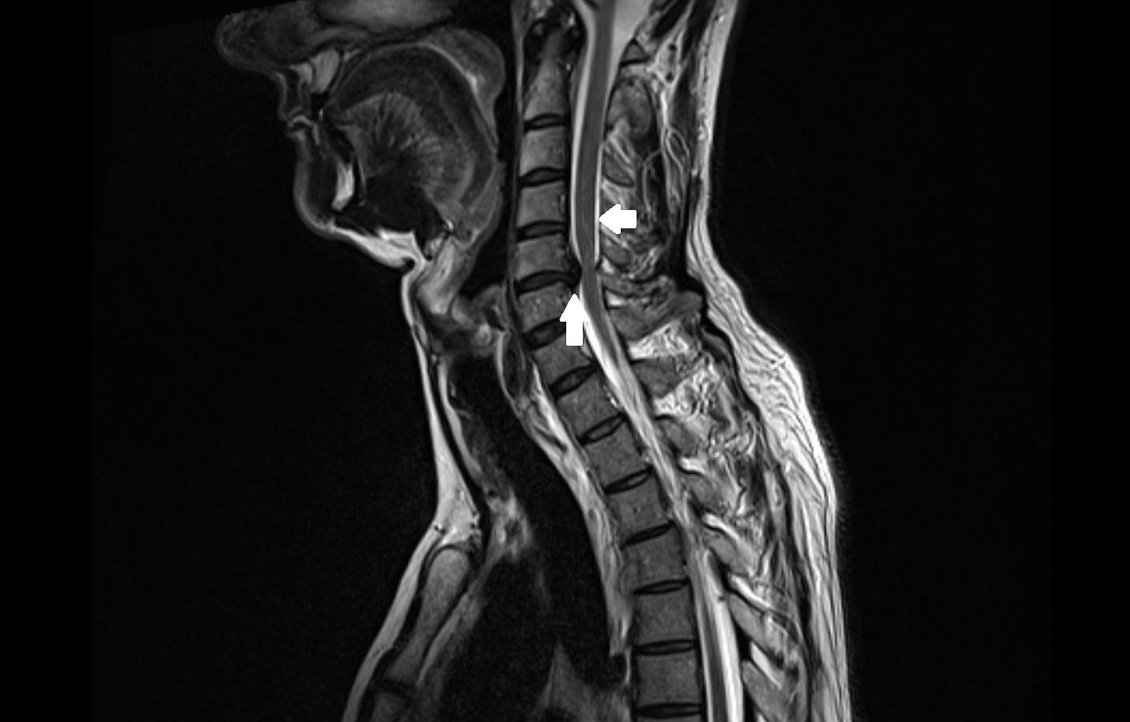

Beschwerden mit der Wirbelsäule sind eine Volkskrankheit: bis zu 80 Prozent der Menschen in industrialisierten Ländern kennen Rückenschmerzen. Die Einschränkung der Beweglichkeit und der Selbstständigkeit können die Folge sein. Die Ursache für ein Leiden an der Wirbelsäule kann sehr unterschiedlich sein und von einer Muskelverhärtung über einen Bandscheibenvorfall, knöchernem und knorpeligem Verschleiß am Achsenskelett bis hin zu Knochenbrüchen und Infektionen reichen.

Unsere Klinik für Neurochirurgie bietet Ihnen das gesamte Spektrum der Wirbelsäulenchirurgie. Besondere Expertise haben wir bei der operativen Behandlung von Abnutzungserscheinungen an der Wirbelsäule, sogenannten degenerativen Veränderungen, und bei der operativen Entfernung von spinalen Tumoren.